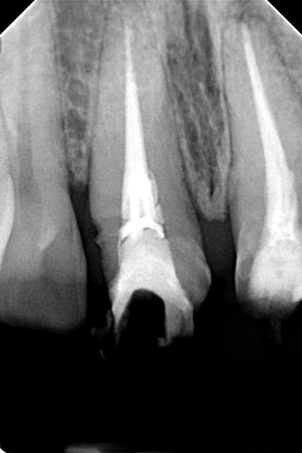

Ο ασθενής πονούσε πολύ στον άνω γομφίο, που είχε απονευρωθεί πριν από χρόνια. Αποφασίστηκε η επανάληψη απονεύρωσης του δοντιού, κατά την οποία διαπιστώθηκε οτι υπήρχε και τέταρτος ριζικός σωλήνας που δεν είχε βρεθεί και επεξεργαστεί κατά την πρώτη προσπάθεια απονεύρωσης. Πλέον το δόντι είναι ασυμπτωματικό.

Παλιά απονεύρωση του δύο άνω γομφίου

Νέα απονεύρωση στον άνω γομφίο

Κλινική εικόνα του τέταρτου ριζικού σωλήνα που βρέθηκε κατά την επανάληψη απονεύρωσης